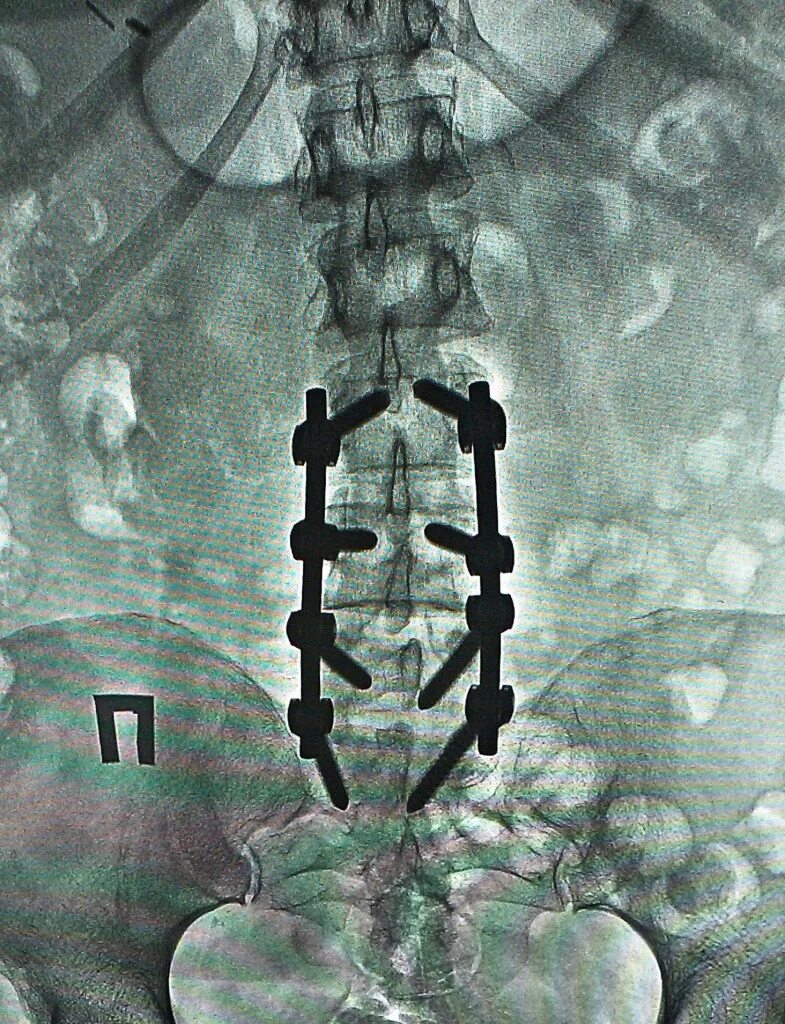

Стабилизирующие операции на позвоночнике